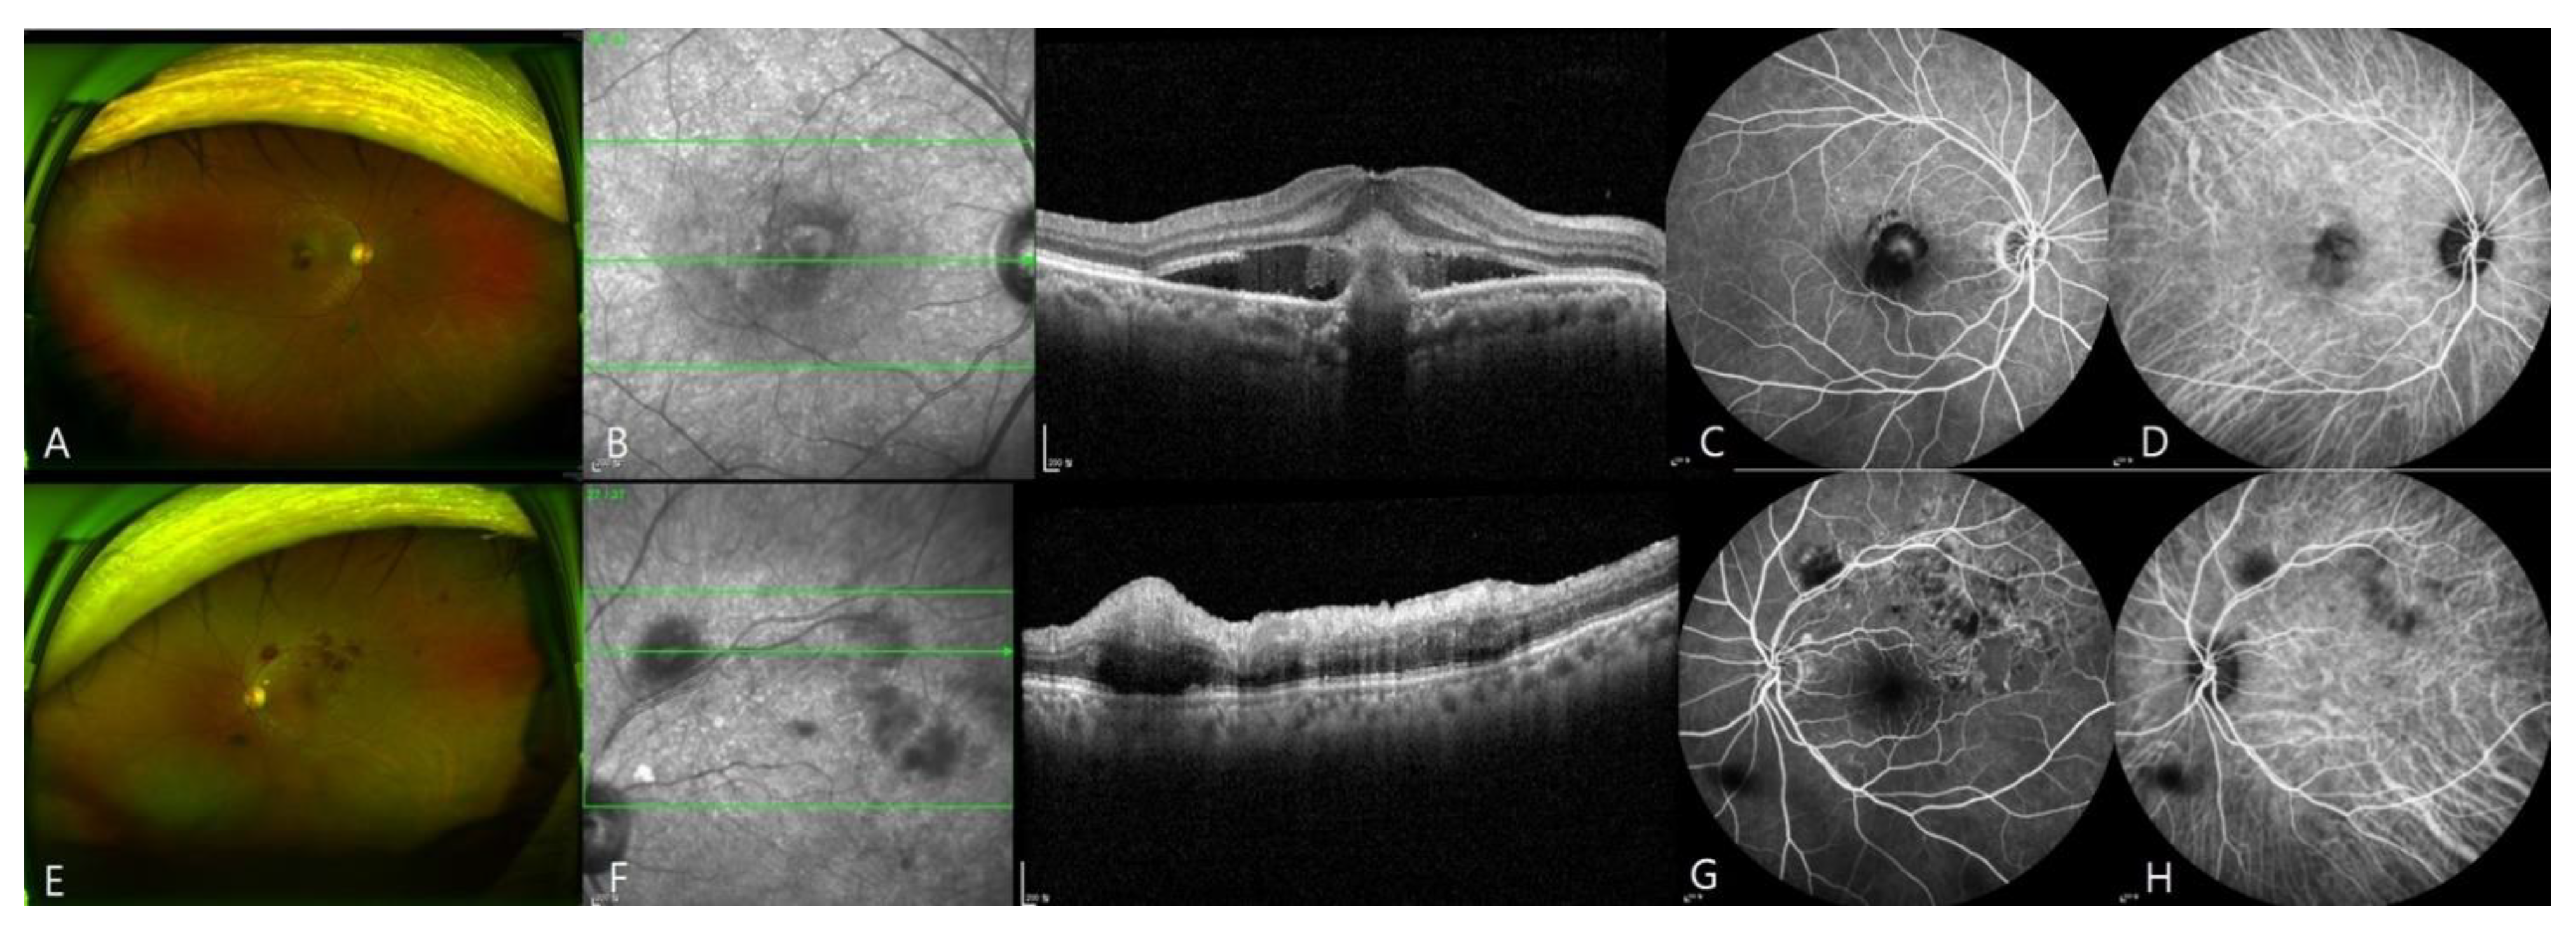

3.1. Submacular Hemorrhage after SARS-CoV-2 Vaccination

3.2. Retinal Vein Occlusion after SARS-CoV-2 Vaccination